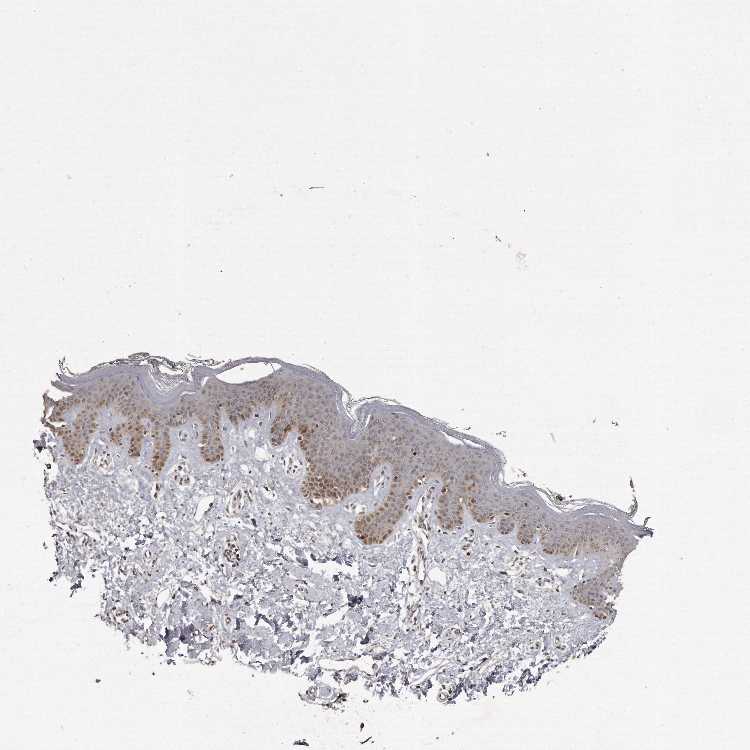

SKIN 1 - Antibody stainingi

Antibody staining in the annotated cell types in the current human tissue is reported as not detected, low, medium, or high, based on conventional immunohistochemistry profiling in selected tissues. This score is based on the combination of the staining intensity and fraction of stained cells.

Each image is clickable and will lead to virtual microscopy that enables deeper exploration of all samples and also displays staining intensity scores, fraction scores and subcellular localization as well as patient and tissue information for each sample.

Antibody HPA028612

Langerhans Medium

Fibroblasts Not detected

Keratinocytes Medium

Melanocytes Medium